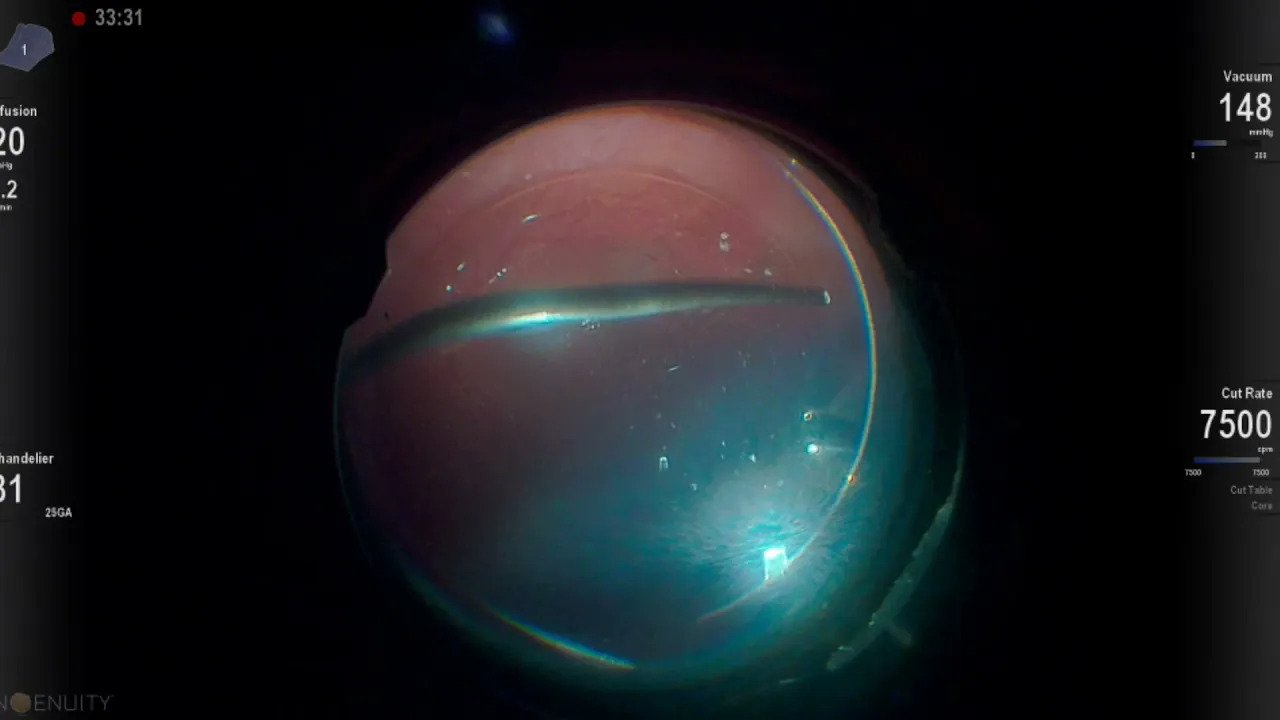

Aici vă prezentăm filmul intervenției de ieri, în urma căreia pacientul (care venise la noi cu vedere extrem de scăzută), a început să vadă mulțumitor de îndată ce i-am dat jos pansamentul, a doua zi.